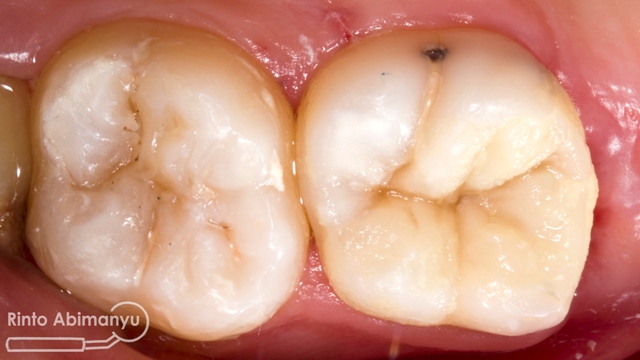

Dilakukan percobaan crown, dicek retensi dan resistensi, integritas tepi, titik kontak, oklusi dan warna… setelah semua tidak ada kendala maka siap dilakukan penyemenan… Semen yang dipakai adalah GIC Fuji I (GC)..

Alhamdulillah prosesnya berjalan lancar dari mulai perawatan saluran akarnya sampai dengan pembuatan crown… mudah2an awet dan tidak ada masalah… amiiiin….